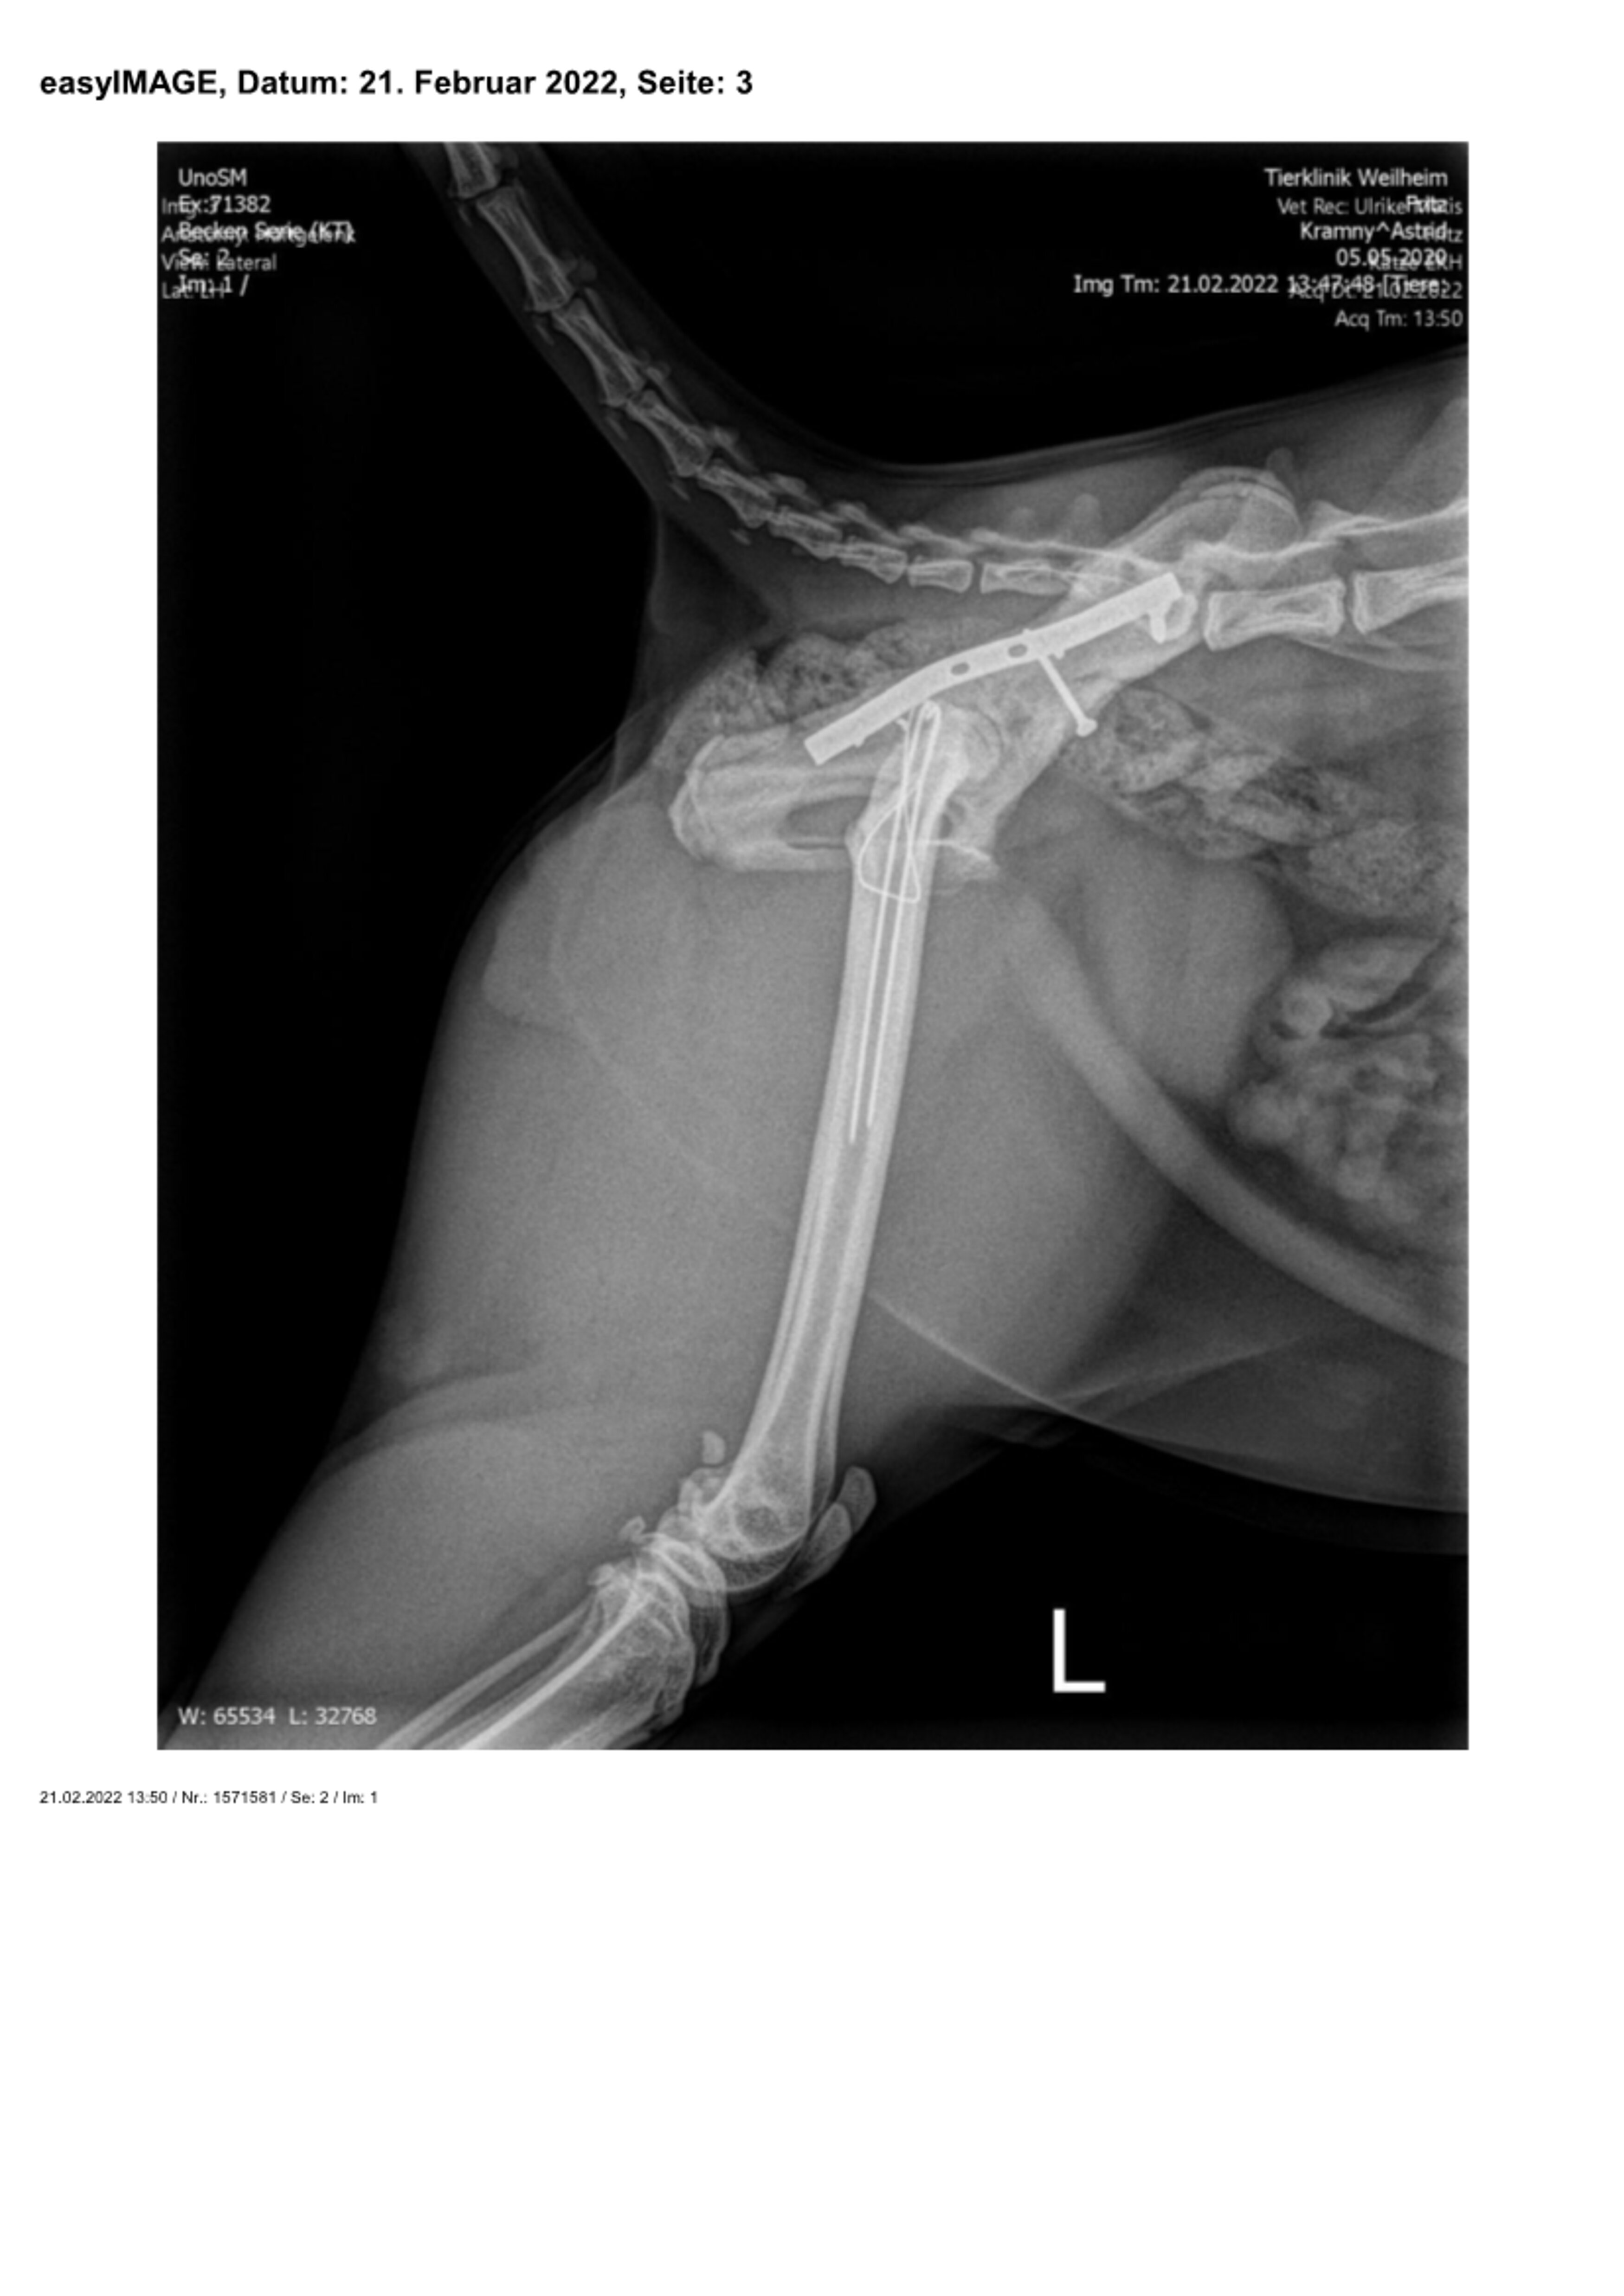

Zuerst wurden das ausgerenkte rechte Kreuz-Darmbein-Gelenk sowie der in seiner unmittelbaren Nachbarschaft verlaufende Ischias dargestellt und das Darmbein nach seiner Reposition mit einer 2,0 mm dicken und 24 mm langen Schraube an den Kreuzbeinkörper fixiert. Nach dem Wundverschluss wurde der Kater auf die andere Körperseite gelagert und sodann der direkt vor der Hüftgelenkspfanne Eine weitere Schraube diente der Adaptation eines Darmbeinsplitters an die Hauptfragmente. Da die Freilegung dieser Beckenregion meistens auch einen Knochenschnitt am Oberschenkel zum Verlagern der Kruppenmuskeln erfordert, wurden die Endsehnen dieser Muskeln mit dem knöchernen Segment abschließend durch 2 Bohrdrähte und einer 8-förmigen Drahtschlinge wiederbefestigt.

Röntgenbilder mit freundlicher Genehmigung Tierklinik Weilheim.

Zu diesem Zeitpunkt war er in der Lage, selbstständig zu stehen. Die Ausfallerscheinungen des Ischias hatten sich durch das Einrenken des rechten Kreuz-Darmbein-Gelenks bereits gebessert. Auch die Stellreaktionen des rechten Vorderbeins, das nach den Röntgenbildern eine Prellung, aber keine Knochenverletzung erlitten hatte, waren schon wieder fast normal. Noch deutlicher waren die neurologischen Fortschritte beim Entfernen der Hautfäden eine Woche später. Trotz der positiven Entwicklung musste jedoch zur Ruhighaltung des Patienten für mindestens sechs Wochen geraten werden, damit alle Verletzungen des Beckenrings, auch die nicht fixierten Frakturen des Beckenbodens, heilen konnten.